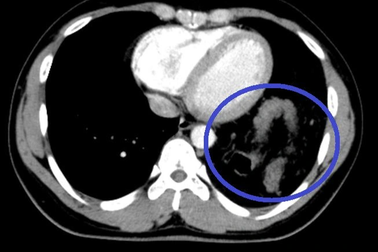

Hy hữu: Vỡ cơ hoành, đại tràng chui lên ngực vẫn tưởng hậu Covid-19Nam bệnh nhân 25 tuổi có tiền sử khỏe mạnh, vào viện khám vì nghĩ ho, khó thở hậu Covid-19. Tuy nhiên, nguyên nhân thực sự gây tình trạng này lại do bệnh nhân vỡ cơ hoành, tạng từ bụng chui lên ngực.